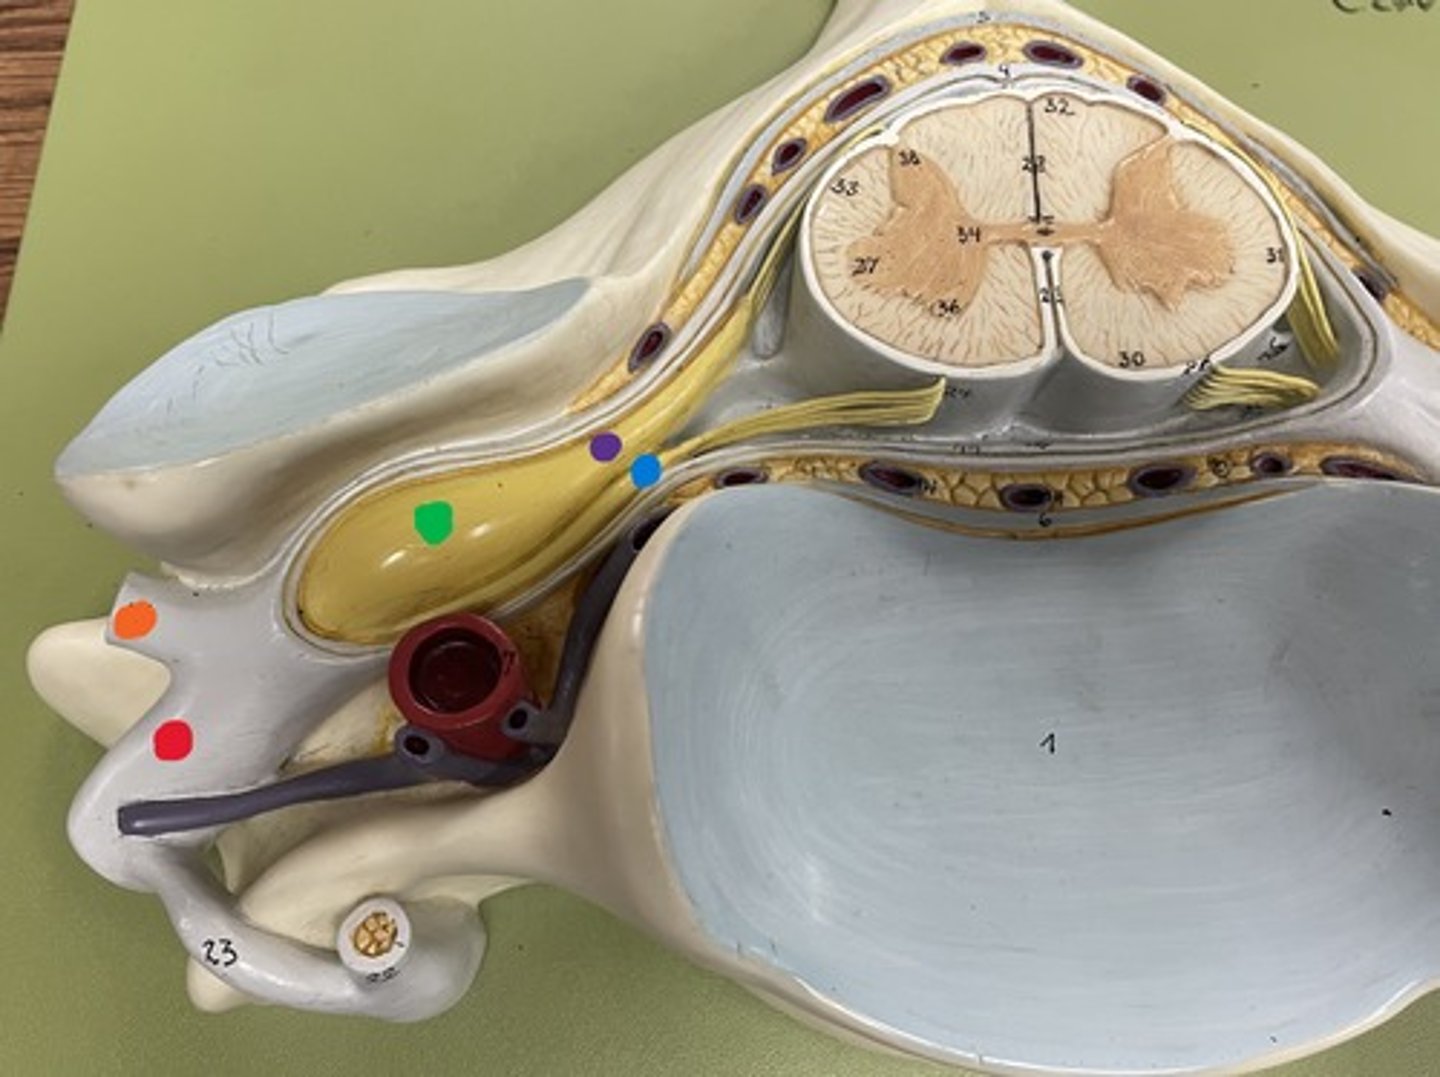

Cervical enlargement

Blue

Lumbar enlargement

Purple

Conus medullaris

Green

Cauda equina

Red

Filum terminale

blue

Epidural space

purple

Subdural space

between red and blue

Subarachnoid space

between red and green

Posterior root

purple

Posterior root ganglion

green

Posterior ramus

orange

Anterior root

blue

Anterior ramus

red